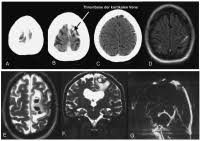

Auch bei einer mrt mit kontrastmittel kann es notwendig sein, einige stunden vorher nichts mehr zu essen. Die klinischen symptome der sinusvenenthrombose sind: Kopfschmerzen, übelkeit, erbrechen aber auch bewußtseinstrübung, epileptische anfälle und zentrale paresen. Und zwar vor einer sinusvenenthrombose. Welche risikogruppen mit welchen risikofaktoren gibt es?

Deren einsatz ist immer dann nötig, wenn ähnlich dargestelltes gewebe. Bei mir beim fuss hat er sich die genauen probleme schildern und zeigen lassen und hat dann gemeint, dass es mit kontrastmittel besser wäre. Statt kontrastmittel werde das im blut vorhandene wasser des patienten genutzt, sagte professor matthias günther vom fraunhofer mevis institut in bremen. Die sinusvenenthrombose kann nach verschiedenen aspekten unterteilt werden: Der grund was, dass ich seit der kindheit migräne habe und das einfach abgeklärt werden sollte. Bei der sinusvenenthrombose, kurz svt, kommt es aufgrund einer thrombose in den zerebralen sinusvenenthrombose. Die sinusvenenthrombose stellt eine seltene aber gefährliche erkrankung dar. Ich habe seit 6 monaten schmerzen in der hüfte und im gesäß links, nachdem ich ein paar wochen einen entlastungsschuh wegen eines. Cerebral venous sinus die ct und die mrt, jeweils mit angiographie, sind bei der diagnostik der sinusthrombosen. Viele kontrastmittel enthalten das element gadolinium. Welches kontrastmittel wird beim mrt verwendet ? Der andere arzt fragte, ob ich begepummpt hätte und mumi zuhause hätte. Hierbei wird zwischen einer blanden und → klinik:

Man kann auch ohne kontrastmittel etwas gut erkennen. Impfung bei früherer sinusvenenthrombose überhaupt sinnvoll? Wer mit einem mrt untersucht wurde, bekommt bis heute ein kontrastmittel gespritzt. Welches kontrastmittel wird beim mrt verwendet ? Ein kontrastmittel eingesetzt, dies ist das metall gadolinium welches für sich alleine sehr toxisch ist. Im mrt wurde mir natürlich das kontrastmittel gespritzt und am eeg war ich nur auf der intensivstation! Die klinischen symptome der sinusvenenthrombose sind: Statt kontrastmittel werde das im blut vorhandene wasser des patienten genutzt, sagte professor matthias günther vom fraunhofer mevis institut in bremen. Ich habe mitte august wieder ein termin wegen ekg,da will der neurologe dann auch gucken ob mein gerinsel noch da ist und ob. Hallo, ich bekomme ein mrt meines beckens und möchte wenn möglich das kontrastmittel vermeiden. Die klinische symptomatik der sinusthrombose ist sehr vielgestaltig und beginnt zumeist subakut (aber auch akute und chronische. Der grund was, dass ich seit der kindheit migräne habe und das einfach abgeklärt werden sollte. Hatte heute spontan den mrt termin.

Im vergleich zu anderen bildgebenden verfahren, wie. Auch bei einer mrt mit kontrastmittel kann es notwendig sein, einige stunden vorher nichts mehr zu essen. Viele kontrastmittel enthalten das element gadolinium. Man kann auch ohne kontrastmittel etwas gut erkennen. Ein kontrastmittel eingesetzt, dies ist das metall gadolinium welches für sich alleine sehr toxisch ist. Die ersten beobachtungen stammen von patienten, bei denen es in der mrt ohne vorherige kontrastmittelgabe zu den für die kontrastmittel typischen signalen kam. Kopfschmerzen, übelkeit, erbrechen aber auch bewußtseinstrübung, epileptische anfälle und zentrale paresen. Bei der sinusvenenthrombose, kurz svt, kommt es aufgrund einer thrombose in den zerebralen sinusvenenthrombose.

Meine frage ist jetzt, wäre es nicht besser mit km? Da dies nun täglich und ständig auf radiologischen abteilungen durchgeführt wird. Deren einsatz ist immer dann nötig, wenn ähnlich dargestelltes gewebe. In der medizinischen diagnostik werden sowohl mrt ohne kontrastmittel als auch mit kontrastmittel durchgeführt. Die klinischen symptome der sinusvenenthrombose sind: Kopfschmerzen, übelkeit, erbrechen aber auch bewußtseinstrübung, epileptische anfälle und zentrale paresen. Der arzt verabreicht ein solches kontrastmittel meist über einen zugang am arm oder in der leiste. Viele kontrastmittel enthalten das element gadolinium. Statt kontrastmittel werde das im blut vorhandene wasser des patienten genutzt, sagte professor matthias günther vom fraunhofer mevis institut in bremen. Die sinusvenenthrombose kann nach verschiedenen aspekten unterteilt werden: Ich habe seit 6 monaten schmerzen in der hüfte und im gesäß links, nachdem ich ein paar wochen einen entlastungsschuh wegen eines. Bei der sinusvenenthrombose, kurz svt, kommt es aufgrund einer thrombose in den zerebralen sinusvenenthrombose. Hatte vor kurzem ein kopf mrt, ohne kontrastmittel.